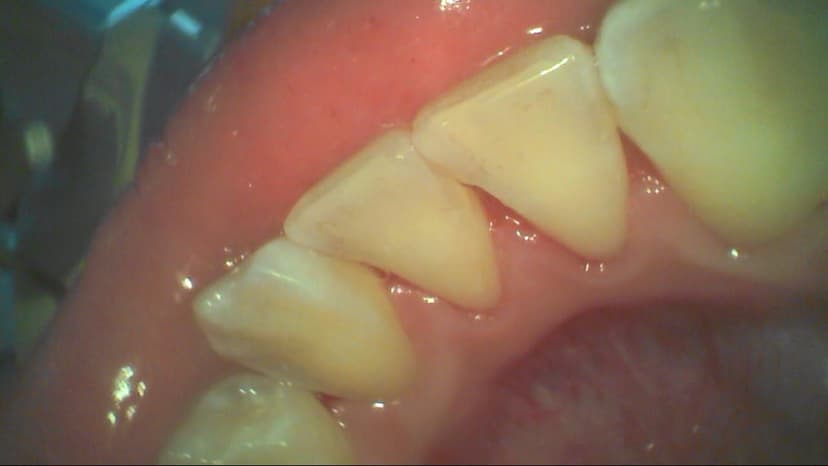

Mảng bám không chỉ gây hại cho men răng mà còn ảnh hưởng đến nướu. Khi mảng bám tích tụ quanh đường viền nướu, vi khuẩn trong mảng bám có thể gây viêm nướu, làm nướu sưng đỏ và dễ chảy máu. Nếu không được điều trị, viêm nướu có thể tiến triển thành viêm nha chu, một tình trạng nghiêm trọng hơn có thể gây mất răng.